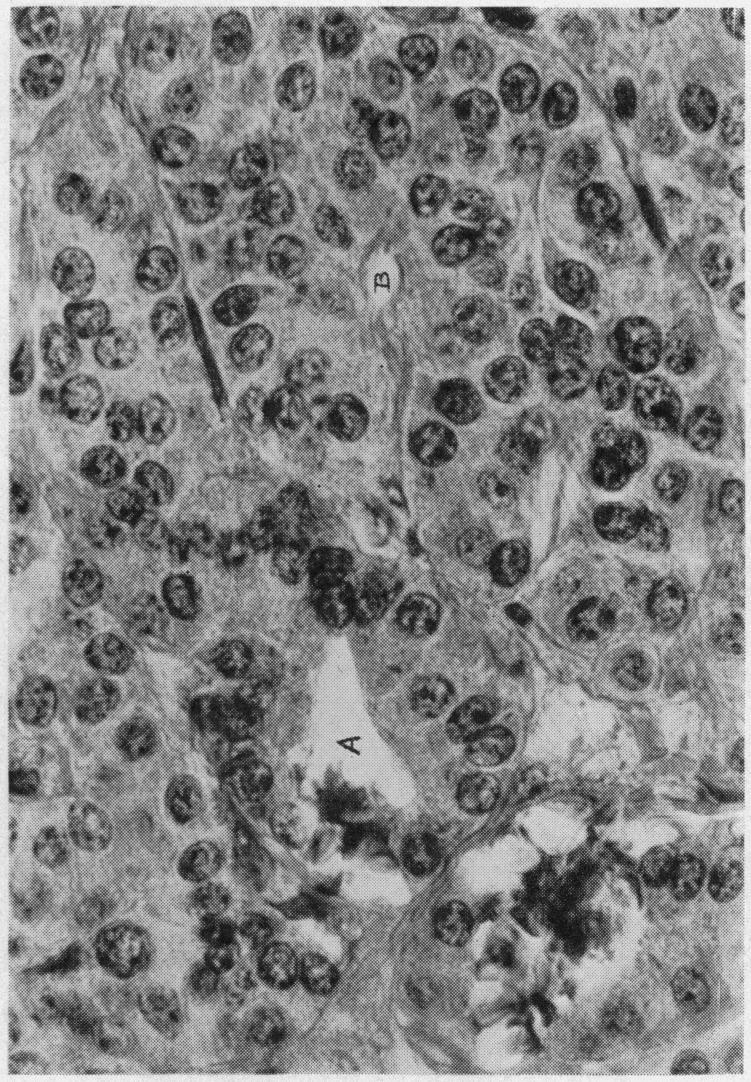

ADENOMA OF ISLET CELLS WITH HYPERINSULINISM: A REVIEW.

Ann Surg. 1935 Jun;101(6):1299-335. doi: 10.1097/00000658-193506000-00001.